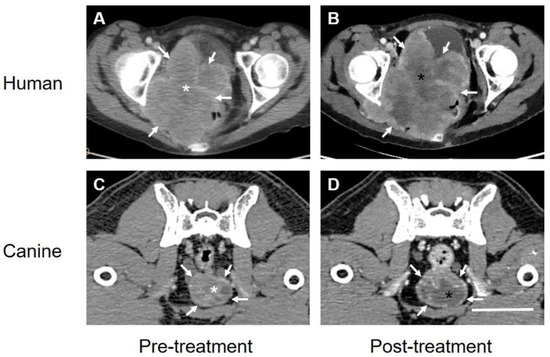

- Paul, D.; Maggi, P.; Piero, F.D.; Scahill, S.D.; Sherman, K.J.; Edenfield, S.; Gould, H.J., III. Targeted Osmotic Lysis of Highly Invasive Breast Carcinomas Using Pulsed Magnetic Field Stimulation of Voltage-Gated Sodium Channels and Pharmacological Blockade of Sodium Pumps. Cancers 2020, 12, 1420. [Google Scholar] [CrossRef] [PubMed]

- Gould, H.J., III; Miller, P.R.; Edenfield, S.; Sherman, K.J.; Brady, C.K.; Paul, D. Emergency Use of Targeted Osmotic Lysis for the Treatment of a Patient with Aggressive Late-Stage Squamous Cell Carcinoma of the Cervix. Curr. Oncol. 2021, 28, 2115–2122. [Google Scholar] [CrossRef] [PubMed]